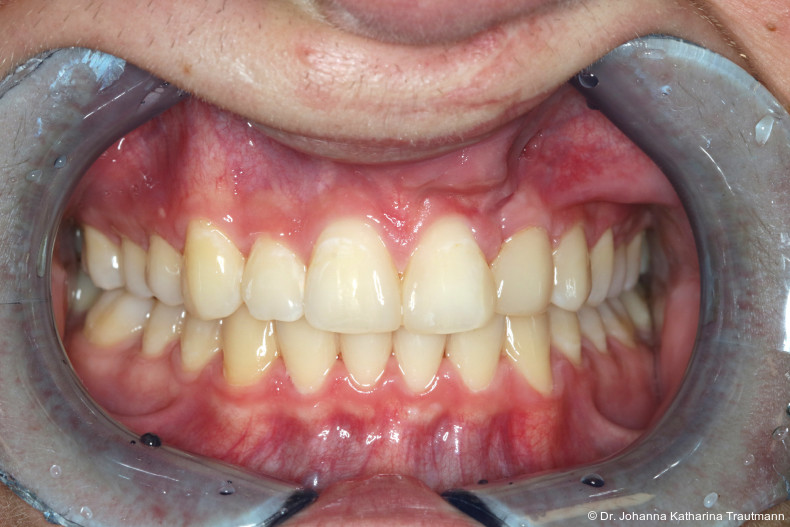

Längere Retentionszeiten ohne odontoplastischen Umbau können das Risiko eines Rezidivs des Zahnes 22 erhöhen. Dennoch ist häufig eine Abheilphase nach der Multibrackettherapie erforderlich, da sich gingivale Entzündungen oft erst nach ein bis drei Monaten vollständig zurückbilden.19–21 Um diesen Zeitraum zu überbrücken wurde an 22 die Kunststoffbasis der DVP (Doppel vorschubplatte) zur Retention sowohl mesial als auch distal extendiert. Schließlich wurden die Zähne 11, 21 und 22 kompositrestaurativ angeglichen, wodurch ein sehr gutes ästhetisches Ergebnis erzielt wer den konnte. Aufbauten mit Komposit bieten eine gute Möglichkeit, bei maximaler Schonung der Zahnhartsubstanz hypoplastische Zähne langfristig zu versorgen, und zeigten in ZehnJahresFollowups hohe Überlebensraten. Entscheidend ist hierbei eine ausgeglichene okklusale Lastverteilung, die mit hilfe einer physiologischen Frontzahnabstützung und gesicherten Okklusion durch die kieferorthopädische Vorbehandlung erreicht werden kann.22

Zur objektiven Quantifizierung des Behand lungsergebnisses wurde der Peer Assess ment Rating(PAR)Index erhoben.23 Im vorliegenden Fall konnte der PAR-Wert von 25 auf zwei reduziert werden, was einer Verbes serung von 92 Prozent entspricht und als hoch wertiges okklusales Ergebnis einzustufen ist.24 Zur Vorhersage der Langzeitstabilität bei Spalterkrankungen lässt sich dieser Fall in die Gruppe 1 des GOSLON Yardstick Index ein ordnen. Dieser sagt eine exzellente Langzeitstabilität vorher.25 Auch der Patient zeigte sich mit dem Ergebnis sehr zufrieden. Während der anderthalbjährigen Retentionsphase erfolgte zusätzlich eine ästhetische Nasenkorrektur zur Aufrichtung des linken Nasenflügels, wodurch neben der dentalen auch die extraorale Rehabilitation erfolgreich abgeschlossen werden konnte.